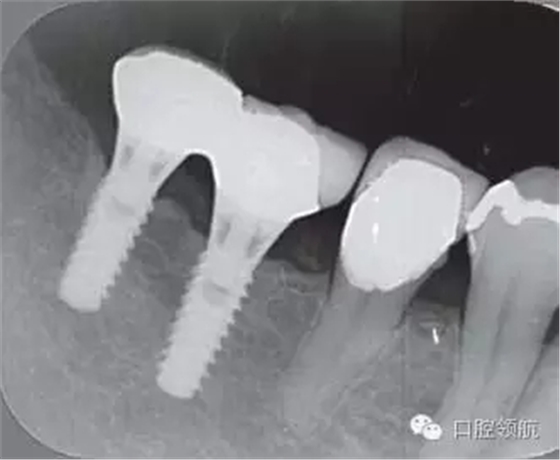

2005年4月時,可見(左下第6顆牙) 部的種植體達到第4螺紋,(左下第7顆牙)的種植體周圍觀察到位于第3螺紋的頸部進行性骨吸收(圖4)。到2009年9月時,骨吸收像的周圍有了明顯的骨密度增加影像(圖5)。

圖4 (左下第6顆牙)的種植體達到第4螺紋, 7 的種植體達到第3螺紋的頸部進行性骨吸收現(xiàn)象(2005年4月)。

圖5 骨吸收像的周圍有了明顯的骨密度增高影像(2009年9月)

這種骨吸收影像,伴隨的不是淺碟狀骨吸收而是與種植體長軸平行方向伴有骨密度增高的骨吸收像,因為沒有發(fā)現(xiàn)口腔內(nèi)有任何炎癥表現(xiàn),所以判斷是否有因夜間磨牙而引起的外傷性骨吸收,于2003年8月為其制作了夜間用防護牙合墊。直到2005年4月復診時由于防護墊沒有得到充分的利用,而導致出現(xiàn)進一步的骨吸收。此后牙合墊開始得到充分的使用。2007年10月時,可以看到(左下第6顆牙) 部的骨吸收情況有所恢復(圖6),2010年12月,(左下第7顆牙) 的骨吸收也有所恢復(圖7)。